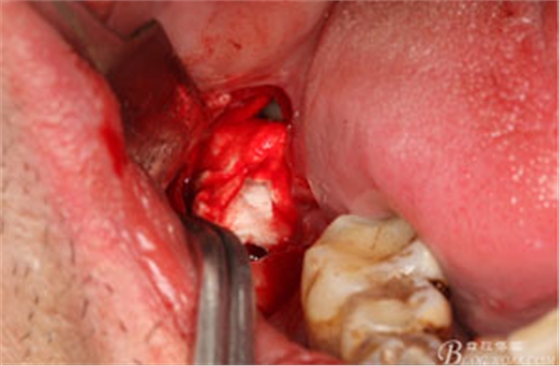

圖14.清理拔牙創(chuàng),并放置膠原蛋白海綿。

圖15.縫合: